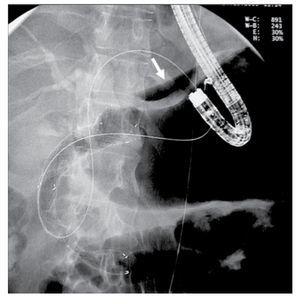

A 43 year-old male with unresectable pancreatic head adenocarcinoma diagnosed 3 months before, was admitted because of incoercible vomiting and jaundice (bilirrubin level of 9.4 mg/dL). Gastroscopy showed tumoral infiltration of the duodenal bulb which prevented access to the ampulla. After informed consent process in which we discuss with the patient the available options including EBPD, another endoscopic session was planned in order to treat both digestive and biliary obstructions. Anticipating that EBPD could be necessary, the patient was placed in supine position under sedation with propofol. We started the procedure by deploying of a 14 cm long self-expandable enteral metallic stent (SEMS) (Hanarostent, Sewoon Medical, Korea) through the duodenal stenosis. After placing the duodenal stent we tried to access the second duodenal loop through the stent, but the stenosis was only partially dilated and we could only reach the superior duodenal flexure. This persistent stenosis despite the SEMS prevented us from attempting to perform ERCP. Thus, we inserted a linear array echoendoscope (Pentax 3630) into the stomach on a straightened position. We scanned the left liver lobe until a dilated bile duct near the liver surface was identified and targeted with a 19 gauge needle (Echo-Tip, Wilson-Cook medical, Inc., Winston-Salem, North Carolina, USA) which we inserted through the gastric wall. We performed an antegrade cholangiography confirming intra and extrahepatic bile duct dilation reaching the intrapancreatic portion, where a 4 cm long stenosis was observed. A 0.35 guide wire was inserted through the needle, and we could gain access through the papilla and made progress with the guide wire into the distal duodenum. After removing the needle, while leaving the guide wire in place, a 7 Fr plastic dilator catheter was introduced over the wire into the distal bile duct and duodenum. Once the fistula was dilated, we tried to insert a 6 cm long partially covered biliary SEMS (Wallstent, Boston Sci, Nattick, MA, USA) through the liver parenchyma with no success, despite repetitive attempts by changing the endoscope angulation. Since we had the distal end of the guide wire in the duodenal lumen, we removed the echoendoscope while leaving the guide wire in place, and inserted a frontal view endoscope through the previously placed duodenal stent until we reached the upper duodenal flexure, from where we could see the guide wire exiting the papilla and forming an intraduodenal loop. We grasped the distal end of the guide wire and extracted it through the mouth, performing an endoscopic rendezvous technique. Once we had both ends of the guide wire coming out through the mouth, we inserted the endoscope over the transgastric portion of the guide wire until we reached the gastric lumen. A 5 mm perforation originated in the parietal fistula with evident pneumoperitoneum was detected after air insufflation (Figure 1 and 2). In view of this situation, we decided to insert a transgastric partially covered SEMS communicating the left bile duct and the gastric lumen, in order to treat the biliary occlusion and seal the gastric perforation. Using now the frontal view endoscope and slightly pulling both ends of the guidewire, we were able to easily insert and deploy an 8 cm SEMS (Wallstent, Boston Sci, Natick, MA, USA) sealing the gastric perforation (Figure 3) and confirming bile flow to the stomach. Immediately after the exploration the patient referred mild abdominal discomfort which eased in a few hours. Twenty four hours later the patient was asymptomatic and a plain abdominal x-ray showed persistence of pneumoperitoneum. He resumed oral feeding with good tolerance 72 hours after the endoscopic procedure and was discharged asymptomatic seven days later with a bilirubin value of 2.4 mg/dL.

¿ Figure 3. A partially covered biliary SEMS was deployed through the gastric fistula communicating the left bile duct and the gastric lumen, sealing completely the teared fistulary orifice in the stomach.